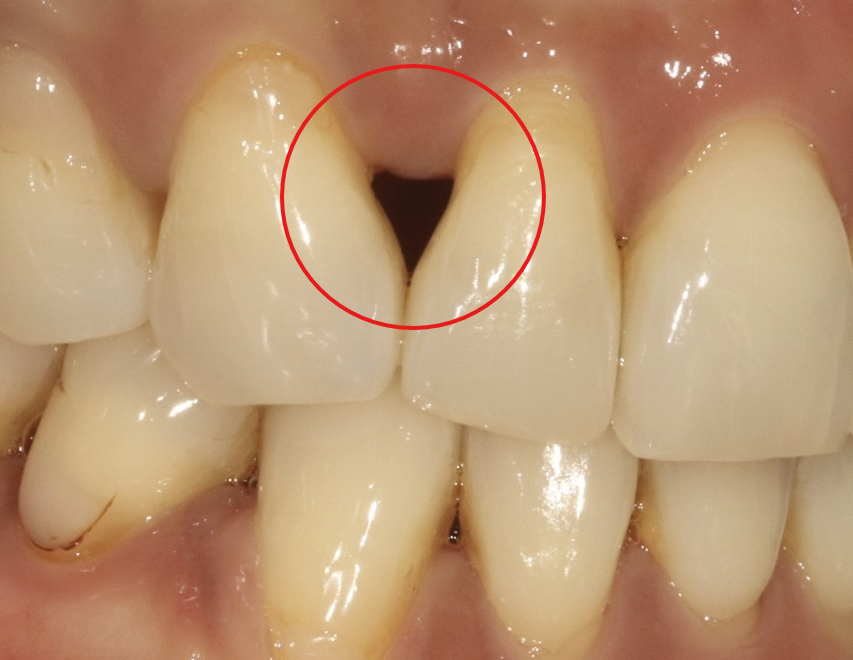

2. 교정 치료 후

교정 치료 자체가 나쁜 것은 아닙니다.

하지만 치아를 이동시키는 과정에서 잇몸이 약간 내려가는 경우가 있습니다.

교정 전에는 치아가 겹쳐 있어서 보이지 않던 잇몸 사이 공간이, 치아가 가지런히 정렬되면서 드러나게 되는 것이죠. 모든 분에게 나타나는 것은 아니지만, 교정 후 블랙 트라이앵글 때문에 고민하시는 분들이 적지 않습니다.

잇몸 필러, 블랙 트라이앵글의 새로운 해결법

블랙 트라이앵글을 개선하는 방법에는 여러 가지가 있지만, 최근 주목받고 있는 방법 중 하나가 바로 잇몸 필러 시술입니다.